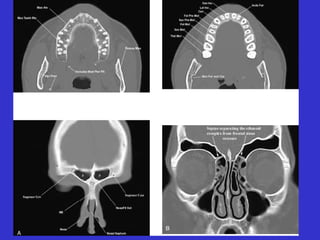

Este documento describe las diferentes proyecciones radiográficas utilizadas para examinar los senos paranasales, incluyendo las proyecciones básicas de Caldwell, Waters lateral y las proyecciones especiales como Hirtz y Waters mentonasal. También describe las diferentes estructuras anatómicas que componen el complejo ostiomeatal anterior y posterior de los senos paranasales.